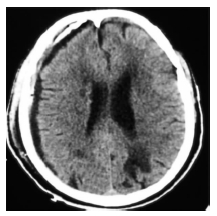

钻孔冲洗引流术与开颅血肿清除术是目前治疗亚急性硬膜下血肿较为常见的术式。钻颅冲洗引流术由于操作简单、创伤小等优点而被广泛采用,但存在一定复发比例[3]。如何减少术后复发,成为目前关注的焦点。彻底冲洗血肿的内容物,纠正凝血机制障碍是防止术后复发的关键。血肿的复发率与术后颅内积气、积血残余过多、血肿存在多房结构明显相关[4]。针对这些问题,笔者总结治疗要点如下:(1) 术中用生理盐水反复冲洗,将局部的纤溶物质及纤维蛋白降解产物尽可能地冲洗掉,直至引流液色清亮,并使残余的陈旧性血液随着大脑的复张尽可能排出。治疗组的一例连续头颅CT检查中(图 1-4),术后1 h头颅CT提示亚急性硬膜下血肿大部份清除,中线回位良好,右侧脑室显影,但局部仍有高密度影及积气。连续冲洗1 d后,高密度影消失,且积气基本消失,中线基本居中,右侧脑室显影更完全,但冲洗后的引流液仍有暗红色血性成份,连续冲洗2 d后,高密度影及积气完全消失,且冲洗的引流液完全清亮。而对照组一例连续头颅CT检查中,术后1 h头颅CT提示亚急性硬膜下血肿大部份清除,中线回位,右侧脑室显影,但局部仍有高密度影及积气。单纯引流五天后,虽中线基本居中,但引流液仍有少量暗红色血性成份,勉强拔除引流管,14天后又形成了巨大的慢性硬膜下血肿。因此,我们认为如果仅靠血肿腔内的残余液体,很难达到充分盥洗的效果,故术后给予持续冲洗是必要的。双腔引流管流入道与流出道完全分开,可实现持续不间断地冲洗引流,有利于将颅内的空气及血性成份排出,增强冲洗效果。(2) 预防气颅:手术过程中,使骨窗位于术野最高位,轻轻摇动头部同时,冲洗生理盐水,尽量排出积气。引流管朝向额叶方向,尽量达到血肿前端边缘,且Y-型双腔引流管的引流端开口位于引流管最前端,这样经Y-型双腔引流管冲洗端用生理盐水冲洗时,可迅速将颅内气体排出。术后根据复查CT情况后给予生理盐水持续灌洗,可尽快排除颅内积气。我们认为引流管朝向额叶方向,尽量达到血肿最前端较既往引流管头端只至血肿中间相比可以较快地排出血肿上端的气体,从而减少气颅的发生。(3) Ohba[5]和Nakaguchi等[6]认为,引流管朝向额叶方向放置可以较快地排出血肿上端的气体,有效降低SSDH 的复发。其不足是血肿下端的残余成份排出缓慢。我们采用Y-型双腔引流管朝向额叶方向,尽可能达到血肿前端边缘,同时根据血肿大小自行在Y-型双腔引流管引流腔加孔4个引流口使引流腔8~9 cm的长度上存在8~9个引流口。既可通过持续灌洗生理盐水而尽快排出血肿上端的气体,又能较快地稀释血肿并通过引流口排出骨孔平面以上的血性成份,但血肿骨孔平面以下的血性成份,则只能靠脑组织复位后的“挤压”作用排出,或嘱患者间断采用俯卧位以便血性成份排出。(4) 引流管通畅与否决定引流效果,从而最终影响手术效果。我们采用了自行设计的防堵引流器。正常引流时,打开止液夹B1,此时弹性引流器内压力同外界大气压,引流系统同标准侧脑室引流系统。如果引流系统堵塞关闭止液夹B2后,通过挤压弹性引流器配合开放、关闭止液夹B1,即可产生负压,从而起到抽吸引流系统的作用。体外实验证明:在充满液体的密闭环境下,长55 cm的12 f(2.2 mm内径,硬度60A)引流管前端被堵塞时,一次尽可能排出弹性引流器内的气体后,可以在引流管前端产生-27.3~-28.1 kpa的负压,该负压可以保证引流的通畅。(5) 灌洗液要维持在35℃左右,避免温差过大诱发血管痉挛。(6) 本组并无感染病例发生,但是否会增加感染还需进一步观察。笔者认为,Y-型双腔引流管+持续灌注治疗亚急性硬膜下血肿与传统方法相比可以较快地排出血肿及气体,可以让中线更快地复位。而且操作简单、有效、并发症较少,可以让大部分老年患者避免了开颅血肿清除术,值得推广。